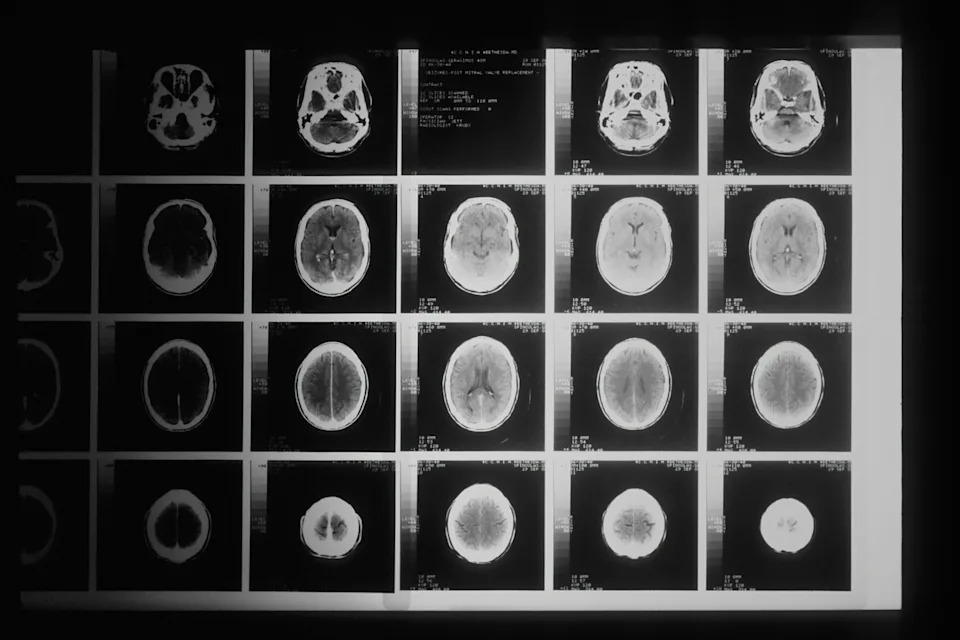

It’s a parent’s worst nightmare: Taking your child to the doctor and receiving a life-changing diagnosis. It only adds to the heartbreak when they find out there may be no effective treatment at all, and that all they can do is hope for the best. Few diagnoses strike fear in the heart of parents and doctors more than a cancer called diffuse intrinsic pontine glioma, or DIPG. Primarily found in children, DIPG is a highly aggressive brain tumor that is uniformly fatal, with less than 10 percent of children surviving longer than two years after diagnosis. The tumors grow fast and on extremely vital areas like the spine and brain stem, making them exceptionally hard to remove. Though young patients have been treated with radiation, chemotherapy, and surgeries, no one had ever been cured of the fatal cancer. But for the first time ever, a 13-year-old boy from Belgium named Lucas Jemeljanova has beaten the odds. Diagnosed with DIPG at age six, Lucas’ doctor Jacques Grill told Lucas’ parents, Cedric and Olesja, that he was unlikely to live very long. Instead of giving up hope, Cedric and Olesja flew Lucas to France to participate in a clinical trial called BIOMEDE, which tested new potential drugs against DIPG. Lucas was randomly assigned a medication called everolimus in the clinical trial, a chemotherapy drug that works by blocking a protein called mTOR. mTOR helps cancer cells divide and grow new blood vessels, while everolimus decreases blood supply to the tumor cells and stops cancer cells from reproducing. Everolimus, a tablet that’s taken once per day, has been approved in the UK and the US to treat cancers in the breast, kidneys, stomach, pancreas, and others—but until the BIOMEDE clinical trial, it had never before been used to treat DIPG. Though doctors weren’t sure how Lucas would react to the medication, it quickly became clear that the results were good. “Over a series of MRI scans, I watched as the tumor completely disappeared,” Grill said in an interview. Even more remarkably, the tumor has not returned since. Lucas, who is now thirteen, is considered officially cured of DIPG. Even after the tumor was gone, Grill, who is the head of the Brain Tumor Program in the Department of Child and Teenage Oncology at Gustave Roussy cancer research hospital in Paris, was reluctant to stop Lucas’ treatments. Until about a year and a half ago, Lucas was still taking everolimus once every day. “I didn’t know when to stop, or how, because there was no other reference in the world,” Grill said. While Lucas is the only one in the clinical trial whose tumor has completely disappeared, seven other children have been considered “long responders” to everolimus, meaning their tumors have not progressed for more than three years after starting treatment. So why did everolimus work so well for Lucas? Doctors think that an extremely rare genetic mutation in Lucas’ tumor “made its cells far more sensitive to the drug,” Grill said, while the drug worked well in other children because of the “biological peculiarities” of their tumors. While everolimus is by no means a cure, the trial has provided real hope for parents and families of children diagnosed with DIPG. Doctors must now work to better understand why Lucas’ tumor responded so well to the drug and how they can replicate those results in tumor “organoids”—artificially-grown cells that resemble an organ. After that, said Marie-Anne Debily, a researcher in the BIOMEDE trial, “the next step will be to find a drug that works as well on tumor cells.” A more recent clinical trial tested a new immunotherapy treatment on young DIPG patients and showed promising results. Many of the patients’ tumors shrank and several participants saw functional improvements in their symptoms and day-to-day lives. But only one of the 11 patients has seen success that rivals Lucas’ — a young man identified only as Drew, who has been thriving tumor-free for over four years after receiving treatment. Once considered a definitive death sentence, there is real hope for the first time. But there’s much more research and work to be done. Until then, however, Lucas’ doctors are thrilled. “Lucas’ case offers real hope,” said Debily. This article originally appeared two years ago. It has been updated. The post A 13-year-old boy has become the first person to be cured of this deadly brain cancer appeared first on Upworthy.